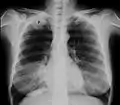

Radiografía de tórax que muestra un tumor de Pancoast (etiquetado como P, carcinoma pulmonar de células grandes, pulmón derecho), de una mujer fumadora de 47 años.